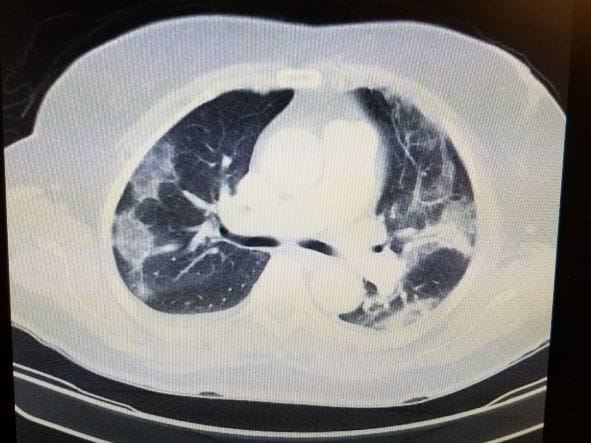

Chest computed tomography (CT)

Chest CT is an imaging tool used as a noninvasive modality for screening and staging lung cancer. It’s fundamental in evaluating lung cancer as it helps define the size, location, and characteristics of lung lesions. Low-dose chest CT has been used to screen cancer in high-risk individuals. This is effective in detecting small lung nodules compared to conventional chest radiography. (2)

A trial demonstration by the US National Lung Cancer Screening Trial shows that using low dose Chest CT to screen individuals with high risk has helped reduce associated mortality by 20%. Even though the patients with positive results need further diagnosis using other procedures, this technology has gone to help with screening and diagnosing lung cancer. (2)